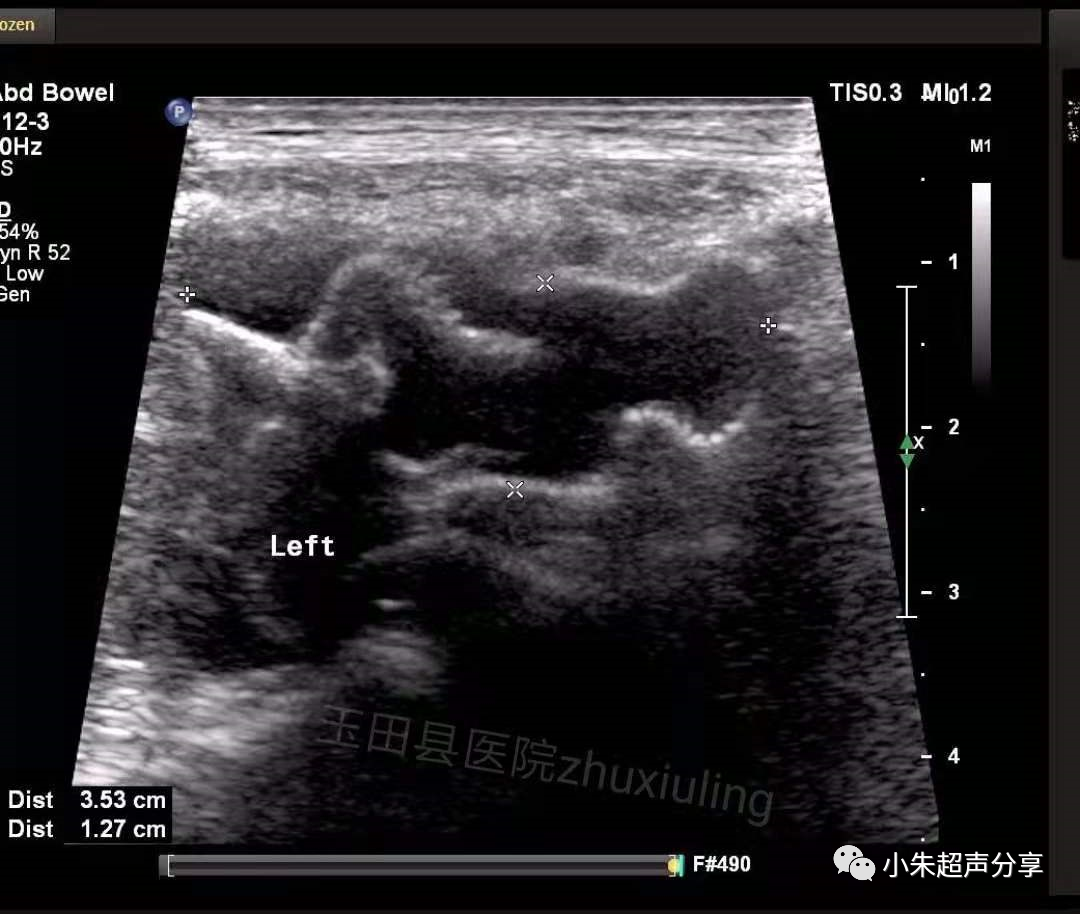

Case2:男,双侧腹股沟疝术后1月,双侧腹股沟区及阴囊疼痛,左侧为著。

超声检查时,置入的补片一般表现为条索样强回声,部分可伴弱声影,周围有积液时显示清晰,无积液衬托时常常显示欠清或难以显示。因补片类型及置入时间的不同,补片的形态亦会有所不同。

血清肿常表现为边界不清、形态不规则、透声差的无回声区,持续时间长者积液内可见多发分隔,无血流信号。在其内部或周边常可见到补片结构,病程长者,补片可卷曲变形呈波浪状(如Case2)。发现时应及时与手术医生沟通,必要时需多次穿刺抽吸,并需定期复查。Case1患者经抽液2次后好转出院(第1次抽出50ml淡红色液体,隔日抽出45ml淡黄色液体)。Case2患者经门诊保守治疗后痊愈。

该2例患者积液发生的部位亦有所不同,Case1患者积液位于右下腹腹腔内并与腹股沟区相通(考虑积液位置为原疝囊内),可能残留狭小缝隙,但未见腹腔内容物疝出;Case2患者积液局限于腹股沟区腹壁软组织内,未见与腹腔相通。